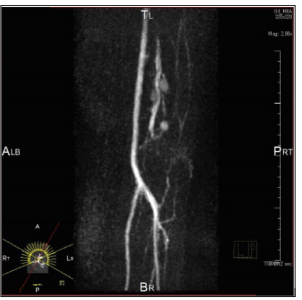

Figure 4: Schwannomas comprehensively diagnosed as a schwannoma in the upper extremity in a 46-year-old female. Magnetic resonance angiography image shows vascular tumors.

Neurilemmomas or Schwannoma: Neurilemmoma, or schwannomas, occur along the course of a peripheral nerve. They may be tender and firm and have a flash- to pale-pink color. Histologically, S-shaped nuclei, Vero cay bodies are characteristic. Both Antoni A and Antoni B tissue may be present. The nervetumor association and vascularity of the tumors could be useful for differentiation of between schwannoma and neuroma. Schwannoma shows eccentric nerve-tumor position on gray-scale US and vascularity within the tumor on color Doppler US [12]. Tsai et al. reported that color Doppler US shows hyper vascular flow signals in a patient with schwannoma [21]. US findings of pathologically confirmed as a schwannoma in the thigh in a 47-year-old male were present as follows: A well-defined hypoechoic nodule with cystic change and eccentric nerve-tumor position were depicted on grayscale US. Blood flow signals were more detectable on power Doppler US than on color Doppler US (Figure 1a-1c). Photomicrograph shows well-defined ovoid mass with degenerative cystic foci. Less cellular Antony type B area consisting of neuronal spindle cells forming Vero cay bodies was detected (Figure 2a- 2c). Tumors were comprehensively diagnosed as schwannomas in the upper extremity in a 46-year-old female were noted as follows: The tumor presents as well-defined hypoechoic nodule without an obviously nerve-tumor position on gray-scale US. Many central blood flow signals were depicted both on color Doppler US and power Doppler US (Figure 3a-3c). Figure 4 shows magnetic resonance angiography image as vascular tumors, suggesting schwannomas. ALM mimic schwannoma very closely. The features of nerve-tumor association and adjacent vessel could be useful for differentiation of between schwannoma and ALM as previously described [7].